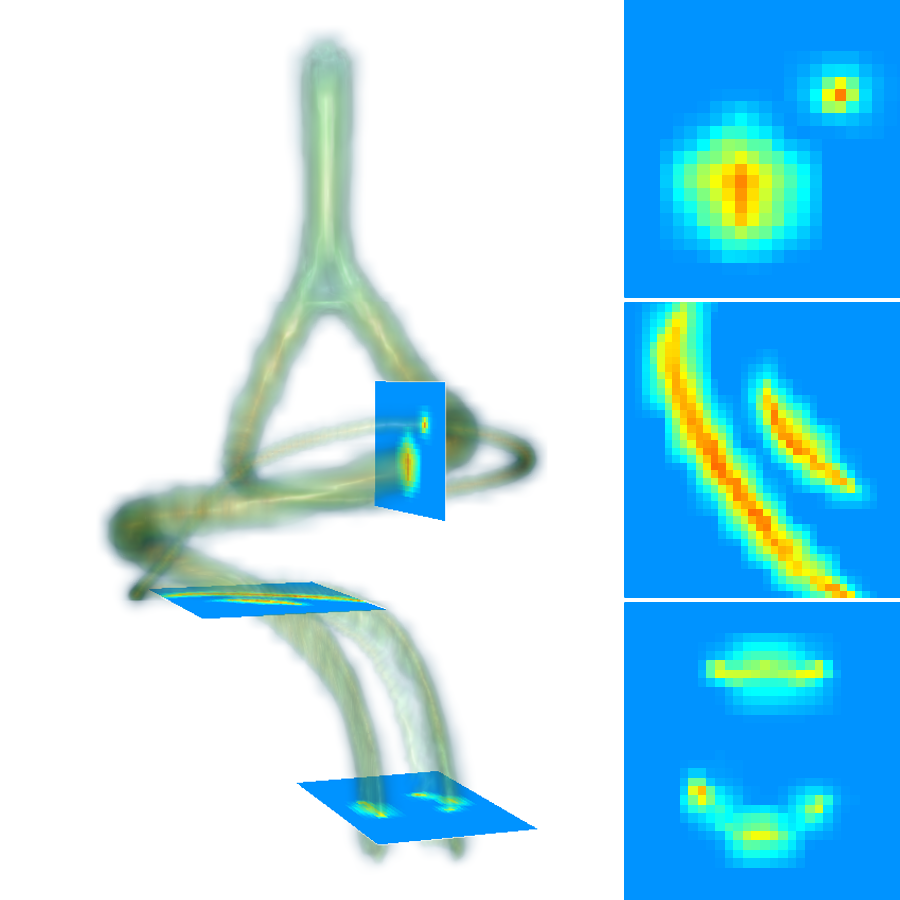

A 3D hand-crafted tortuous and convoluted phantom (HCP) is designed to account for complex vessel patterns, i.e. branching, kissing vessels, scale and shape variations induced by pathologies. Also a set of 20 synthetic vascular trees (SVT) ( voxels) were generated using VascuSynth [10] considering two levels of additional noise (N1: + Shadows: 1 + SaltPepper: ; N2: + Shadows: 1 + SaltPepper: ). Together with the synthetic data, a cerebral Phase Contrast MRI (PC) ( mm), a cerebral Time of Flight MRI (TOF) ( mm) and a carotid CTA ( mm) were used. Vascular network ground-truths (GT) are given in the form of connected raster centerlines for all the synthetic images and for both TOF and CTA.

3.2 Connected Geodesic Paths as Vascular Tree

Representative examples of degraded synthetic images from SVT and the respective GT are shown in fig. 4 together with the connected graphs extracted by VTrails. Analogously, the same set of images are reported for the real images TOF and CTA in fig. 4. Qualitatively, the extracted set of connected geodesic paths shows remarkable matching with the provided GT in all cases. First, we verify the acyclic nature of the graph. We found no cycles, degenerate graphs and unconnected nodes, meaning that the extracted connected geodesic paths represent a connected geodesic tree. Precision and recall are then evaluated for the identified branches. Also, error distances are determined as the connected tree’s binary distance map evaluated at GT. Average errors () precision and recall are reported (meanSD) in table 1. Note that no pruning of any spurious branches is performed in the analysis.